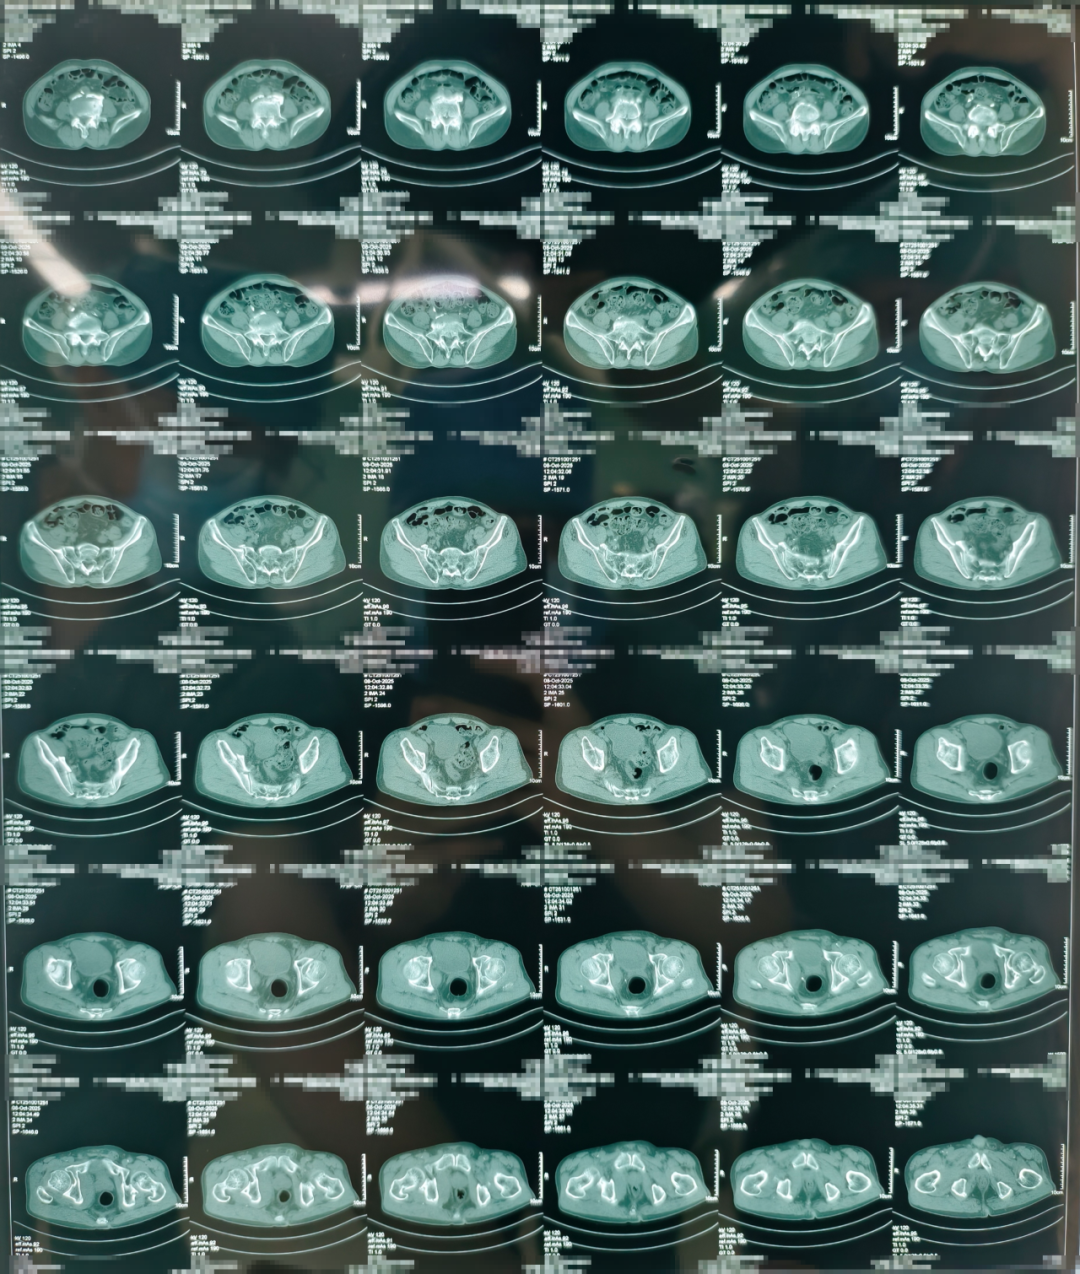

术前

团队通过三维影像重建,为患者量身定制手术路径,数据导入系统后生成个性化复位方案。

点击查看大图